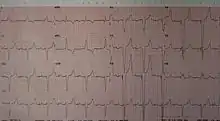

From this the basic ventricular "on demand" pacing mode is VVI or with automatic rate adjustment for exercise VVIR – this mode is suitable when no synchronization with the atrial beat is required, as in atrial fibrillation. The equivalent atrial pacing mode is AAI or AAIR which is the mode of choice when atrioventricular conduction is intact but the sinoatrial node of the natural pacemaker is unreliable – sinus node disease (SND) or sick sinus syndrome. Where the problem is atrioventricular block (AVB) the pacemaker is required to detect (sense) the atrial beat and after a normal delay (0.1–0.2 seconds) trigger a ventricular beat, unless it has already happened – this is VDD mode and can be achieved with a single pacing lead with electrodes in the right atrium (to sense) and ventricle (to sense and pace). These modes AAIR and VDD are unusual in the US but widely used in Latin America and Europe.[13][14] The DDDR mode is most commonly used as it covers all the options though the pacemakers require separate atrial and ventricular leads and are more complex, requiring careful programming of their functions for optimal results.

Automatic pacemakers are designed to be over-ridden by the heart's natural rate at any moment that it gets back to a non-pathologic normal sinus rhythm and can reinitiate influencing the electric activity in the heart when the pathologic event happens again.[15] A "ventricular-demand pacemaker" produces a narrow vertical spike on the ECG, just before a wide QRS. The spike of an "atrial-demand pacemaker" appears just before the P wave.[16]

Comparably, a Triggered Pacemaker is activated immediately after an electrical activity is commenced in the heart tissue by itself. A "ventricular triggered pacemaker" produces the impulse just after a pulse is created in the ventricular tissue and it appears as a simultaneous spike with QRS. An "atrial triggered pacemaker" is the mode in which an impulse is produced immediately after an electrical event in the atrium. It appears as a discharge following the p wave but prior to the QRS which is commonly widened.[17]